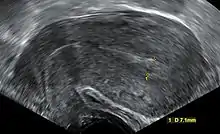

![]() | |

| An ultrasound showing a gestational sac containing a yolk sac but no embryo. | |